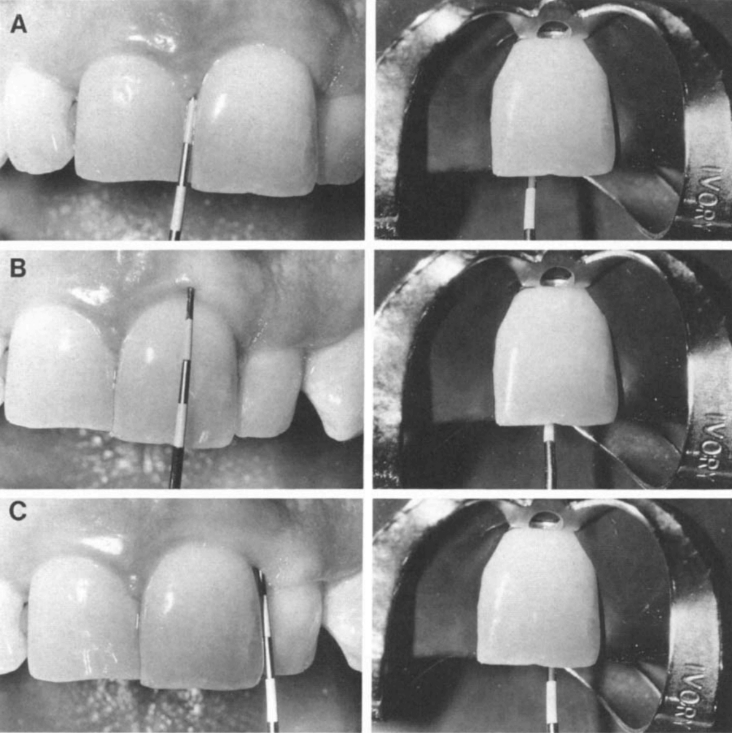

Расположение барьера следует определять путем зондирования уровня прикрепления эпителия. Для определения уровня прикрепления эпителия от резцового края зуба используется мезиальное, дистальное и вестибулярное зондирование. Внутрикоронковый уровень барьера устанавливается на расстоянии 1 мм от соответствующего внешнего выступа крепления (рис. 2). Это определяет корональный контур внутреннего рисунка для определения расположения и формы барьера. Барьер должен проходить в апикальном направлении не менее чем на 2 мм, т.е. иметь толщину не менее 2 мм (12).

Определение уровня прикрепления небного эпителия не столь важно в тех случаях, когда небный барьер остается на прежнем равном уровне или находится по диагонали от ближайшей высоты барьера. Несмотря на то, что это предотвращает обесцвечивание небно-десневой коронковой части, это, по-видимому, не влияет на эстетику вестибулярной поверхности. Форма барьера с вестибулярной стороны напоминает "бобслейный туннель" (рис. 3А). Форма проксимального контура напоминает "лыжный склон" (рис. 3Б). На рисунке 4 схематично изображен барьер. Рентгенограммы внутрикоронкового барьера показаны на рис. 5.

Рис. 2. Пародонтальное зондирование. А, Мезиально. Б, вестибулярно. В, дистально. Зондирование мезиально и дистально следует проводить в срединно-проксимальной области.

Рис. 3. Форма барьера. А, Вестибулярный контур напоминает "бобслейный туннель". Б, Проксимальный контур выглядит как "лыжный склон".